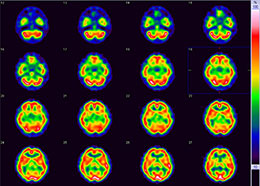

脳血流シンチグラフィ

- 脳内の血流量を画像化する検査です。脳内に病気がある場合、血流量に変化が生じるため、画像でも変化が生じます。

- 血流の量が多い部分はより赤く、少ない部分はより青く表示されます。

- 脳梗塞、一過性脳虚血発作、脳動脈閉塞、もやもや病等の診断に用いられます。

- 脳血流シンチグラフィの画像とMRI等の画像を重ね合わせることで、より正確な部位を把握でき、診断精度も向上します。